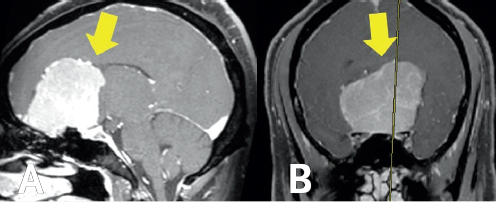

During the same period of time his vision had inexplicably worsened, Robert’s caregiver began to notice additional changes in his personality. Every day, Robert seemed a little less like himself. He was sleeping more than usual and now missing many of the community events he would previously attend. When Robert stopped checking his blood sugar levels and taking his medications, his caregiver felt something was very wrong. In light of both the vision and personality changes, Robert was ultimately referred to a neurologist. In addition to Robert’s deterioration in vision and personality, detailed neurologic testing in neurologic clinic also revealed anosmia or loss of smell with associated deterioration in taste. Anosmia is yet another symptom commonly observed with massive OGMs that often goes initially undetected; progressive enlargement of olfactory groove meningiomas stretches the olfactory nerve(s), often resulting in loss of smell in large or massive OGMs.11 Following thorough evaluation in neurology clinic, magnetic resonance imaging (MRI) of the brain was ordered. These images demonstrated a massive tumor originating from the olfactory groove (Figure 1.1). The tumor extended posteriorly to compress Robert’s optic chiasm—explaining his progressive visual loss. The massive tumor could also be seen to displace and compress both frontal lobes, providing an explanation for the pronounced changes in personality and executive function his family and caregivers had noted. On MRI, the appearance of the tumor was most consistent with an olfactory groove meningioma.

After the report from the MRI returned, Robert was referred to Dr. Jonathan Forbes, a neurosurgeon specializing in skull base tumors. Dr. Forbes explained to Robert that, without surgery, the tumor would continue to grow and further impair his vision and personality. With surgery, Robert’s vision was likely to improve. It was also likely that removal of the tumor would help Robert regain some element of frontal lobe function. Though hearing about the surgery was scary, Robert and his family knew the tumor had to be removed (Figure 1.1A). Dr. Forbes performed a technique often used for large tumors in the anterior skull base called a bifrontal craniotomy (Figure 1.1B).12 After removing a portion of the skull bone covering the frontal lobes, he opened the dura mater—the tough outermost layer of the meninges covering the brain. The tumor was de-vascularized from its origin along the olfactory groove and debulked using a device called a sonopet. The tumor could then be meticulously dissected from adjacent healthy brain tissue. With the aid of high magnification, Dr. Forbes carefully dissected the tumor from Robert’s optic nerves and pituitary stalk. The entire tumor was removed and sent to pathology, confirming a benign meningioma.

(Left) A white blob within a gray space is highlighted by a yellow arrow on the left side of the image. The white blob is surrounded by gray space, which is enclosed by a white outline. (Right) A light gray colored blob within a dark gray space is highlighted by a yellow arrow in the center of the image. It is enclosed by a black circle and white outline.

FIGURE 1.1 MRI demonstrating Robert’s olfactory groove meningioma. Sagittal (A) and coronal (B) images demonstrate a massive olfactory groove meningioma (yellow arrow) resulting in severe compression of the frontal lobe and vital optic structures required for vision.